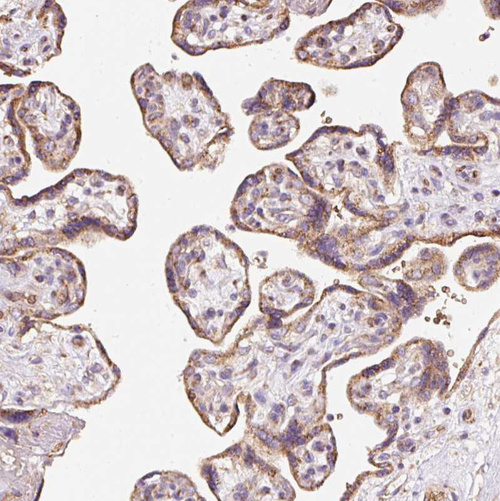

Immunohistochemical staining of human testis shows weak cytoplasmic positivity in cells in seminiferous ducts.